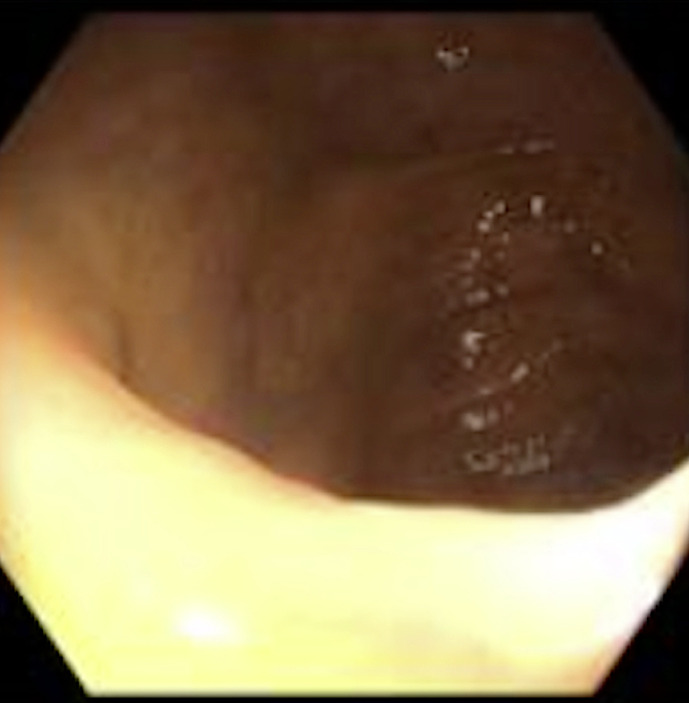

Case presentation: Our patient, a 77-year-old male, underwent an uncomplicated screening colonoscopy and was discharged home after briefly being monitored without any complaints. Later that day, the patient presented to the emergency department complaining of acute generalized abdominal pain. On presentation, the patient was found to be hypertensive and febrile with a distended abdomen with right lower quadrant tenderness on examination. Laboratory investigations noted an elevated white blood cell count with no evidence of acute appendicitis or focal inflammatory changes on contrast-enhanced abdominal and pelvic computer tomography. The patient was subsequently admitted and developed worsening right lower quadrant abdominal pain and distention overnight. Due to this worsening clinical condition, the decision was made to proceed with a diagnostic laparoscopy. After frank pus was found laparoscopically around the cecum and appendix, it was then converted to an exploratory laparotomy. Subsequently, a perforated gangrenous appendix was found with an erythematous and indurated cecum.

Abstract Image